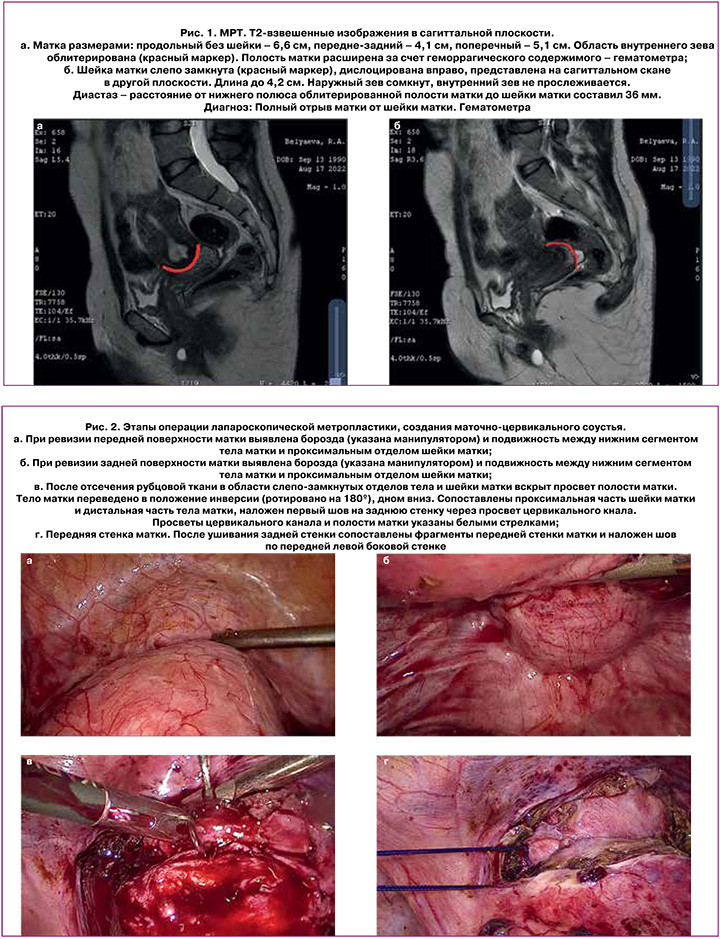

Проведена магнитно-резонансная томография (МРТ). По данным МРТ выявлена картина облитерации внутреннего зева шейки матки, гематометра (рис. 1). Диагноз: Полный отрыв матки от шейки матки. Гематометра.

Описание: Нами описано редкое клиническое наблюдение благополучного исхода беременности и родов в результате оперативного лечения – создания маточно-цервикального соустья после полного отрыва матки от шейки. Диагностика и предоперационное моделирование анатомии внутренних половых органов произведено с использованием магнитно-резонансной томографии. Оперативное лечение полностью выполнено лапароскопическим доступом. Концептуально важными были: мобилизация и анатомирование разобщенных (дислоцированных) сегментов шейки и матки, иссечение рубцовой ткани, ушивание через все слои миометрия, сопоставление сегментов и воссоздание анатомии матки. Период регенерации послеоперационного рубца составил 12 месяцев. Беременность наступила через 6 месяцев после отмены контрацепции, протекала на фоне гестагенной поддержки, установки пессария Арабин. Пациентка родоразрешена путем операции кесарева сечения в сроке 35 недель беременности после проведения курса профилактики респираторного дистресс синдрома плода. При ревизии области послеоперационного рубца видимых дефектов не обнаружено.

Заключение: Представленное редкое клиническое наблюдение полного отрыва матки в результате тяжелой травмы показало высокую информативность визуальной диагностики перед планированием операции. Восстановительная операция, терапия, направленная на пролонгирование беременности и своевременное родоразрешение, позволили достичь рождения здорового ребенка.